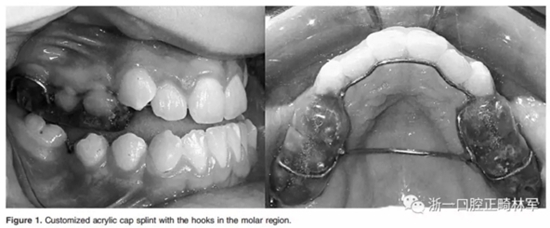

在治療前觀察所有受試者的生長狀況平均5個月(5.366±1.48個月)以觀察他們的生長變化。觀察結(jié)束時,在每位患者上頜牙列磨牙區(qū)定制塑料頜板(Figure 1)。